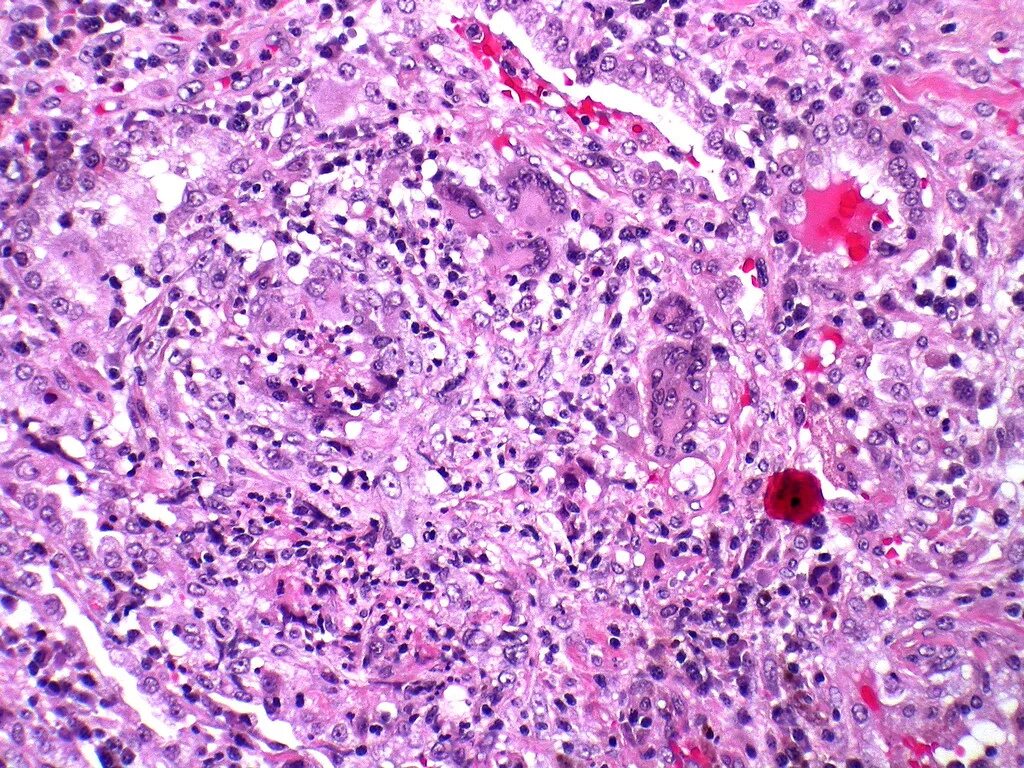

Гранулематоз лечение